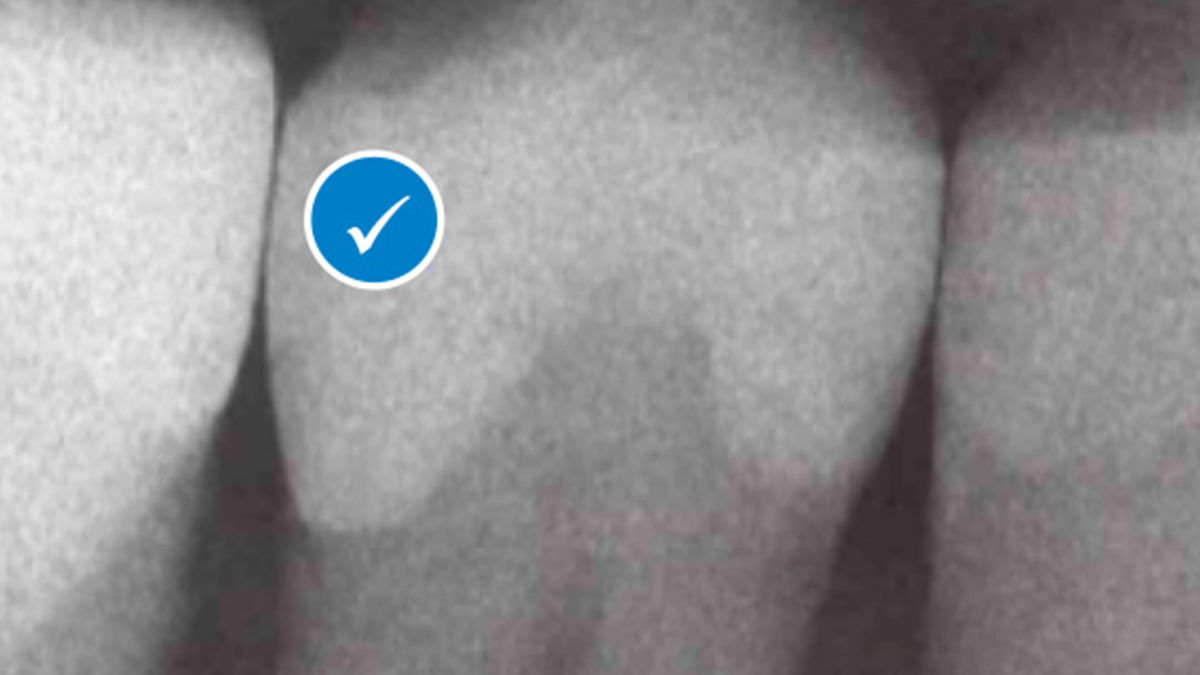

Using SDR® Plus has a number of advantages, including a reduced risk of postoperative sensitivity and enhanced marginal integrity, which is an important factor in the prevention of secondary caries. It also makes the creation of a uniform, void-free restoration easier thanks to the material's self-leveling qualities, and its high radiopacity simplifies monitoring of the restoration over time.

SDR® Plus is indicated for a variety of dental procedures, including the filling of Class I, II, III and V cavities, pit&fissure sealing, and even core build-ups before placing a crown. It is applied in its flowable state through injection from a syringe, or a small capsule called “Compula Tip”. After placement, SDR® Plus gets light cured by the application of blue light (440 – 480 nm wavelength) from a dental polymerization light. This allows the material to create a dense molecular network and replace the tooth substrate that was drilled away as a permanent restoration.